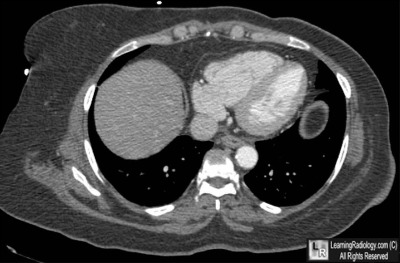

Additional Image-Axial CT of Lower Thorax

Axial CT of Lower Thorax

3. Epicardial Fat Pad

Epicardial Fat Pad

• An accumulation of fat between the parietal pericardium and the parietal pleura, usually found incidentally on chest radiography

• Most common in either the right cardiophrenic angle or adherent to the left ventricle at the apex of the heart

• On the left side, it blunts the normal rounded apex of the heart

• Can be mistaken for pneumonia or a mass